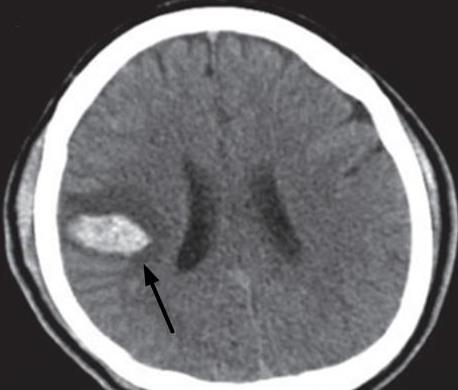

• 神经内镜下不同出血部位高血压脑出血血肿清除手术技巧探讨

2025, 31(7):59-68. DOI: 10.12235/E20240515

摘要 (113) HTML (115) PDF 858.42 K (75) 评论 (0) 收藏

摘要:目的 探讨神经内镜下不同出血部位高血压脑出血(HCH)血肿清除手术技巧及其治疗效果。方法 选取2022年5月-2024年1月该院收治的HCH患者101例,根据CT结果,将患者按照脑出血部位分为脑叶出血组(n = 43)和基底节区出血组(n = 58)。该研究采用Pearson法,分析脑微循环指标与美国国立卫生研究院卒中量表(NIHSS)评分、简易智能精神状态检查量表(MMSE)评分和日常生活能力Barthel指数(BI)评分间的相关性;基于广义估计方程,分析神经内镜下血肿清除术对不同出血部位患者脑微循环指标的改善效果。基于双重差分方程模型,分析神经内镜下血肿清除术对不同出血部位患者NIHSS评分、MMSE评分和BI评分的改善效果,并将基线指标纳入模型作为控制变量。结果 基底节区出血组手术时间明显长于脑叶出血组,NIHSS评分、MMSE评分、BI评分、平均通过时间(MTT)、脑血流量(CBF)、脑血容量(CBV)和平均动脉压(MAP)治疗前后差值变化明显小于脑叶出血组,差异均有统计学意义(P < 0.05);两组患者并发症发生率比较,差异无统计学意义(P > 0.05);相关分析结果显示,MTT与NIHSS评分呈正相关,MTT与BI评分和MMSE评分呈负相关,CBF、CBV和MAP与NIHSS评分呈负相关,CBF、CBV和MAP与BI评分和MMSE评分呈正相关,差异均有统计学意义(P < 0.05);广义估计方程分析结果显示,脑叶出血组MTT、CBF、CBV和MAP改善情况明显优于基底节区出血组,差异均有统计学意义(P < 0.05);双重差分方程模型分析结果显示,年龄增大、MTT延长和发病到手术时间的延长对NIHSS评分产生正影响(B = 0.884、1.291和0.758,P < 0.05),对MMSE评分产生负影响(B = -1.014、-1.569和-0.821,P < 0.05);MTT延长对BI评分产生负影响(B = -0.973,P < 0.05);CBV、CBF和MAP的升高对NIHSS评分产生负影响(B = -0.841、-0.767和-1.213,P < 0.05),对MMSE评分和BI评分产生正影响(MMSE:B = 0.932、0.738和0.874;BI:B = 0.897、0.751和0.842,P < 0.05)。结论 神经内镜下血肿清除术通过调节HCH患者的MTT、CBF、CBV和MAP等指标,可改善HCH患者的NIHSS评分、MMSE评分和BI评分,且脑叶出血患者改善效果明显优于基底节区出血患者。